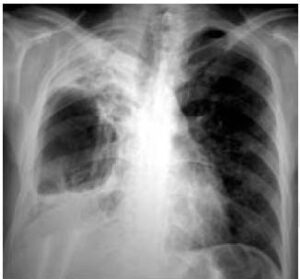

- nel versamento libero appare un’opacità con concavità superiore (disegnando la linea di Ellis-Damoiseau), espansione dell’emitorace e spostamento del mediastino verso il lato sano a seconda della quantità di versamento.

Nel versamento pleurico massivo, se il liquido si accumula sempre di più, si ha un collasso progressivo del parenchima polmonare sottostante che può rendere completamente opaco un emitorace che apparirà completamente bianco.

I segni che ci portano verso la diagnosi sono l’opacità totale di un emitorace, lo spostamento del mediastino verso il lato controlaterale, l’abbassamento del diaframma che può assumere una forma invertita, l’allargamento degli spazi intercostali e assenza di broncogramma aereo (in quanto vi è un aumento di densità, non si vedrà il broncogramma aereo).